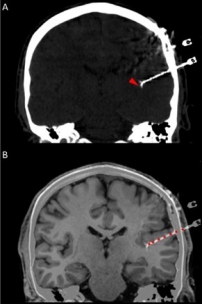

In addition to the very valuable iEEG recordings from the clinical macroelectrodes, our iEEG recordings also include signals recorded with microelectrodes. The additional microelectrodes have a diameter of about 40 μm (smaller than the hair) and spread out of the tip of the clinical intracranial electrode. They are added solely for research purposes and, because of their small size, they can record the electrophysiological firing activity generated by nearby individual neurons. We analyze this data by using algorithms which classify the different waveforms recorded by a single microwire into action potentials generated by different neurons. We also use population decoding methods to extract the information associated by the neurons (e.g. “concept” neurons which preferably fire in response to specific images of the same individual). To localize the site of the macro- and micro-electrodes with high spatial resolution, we combine post-implantation CT scans with pre-implantation neuroimaging scans from the 7-Tesla MRI, available at the University of Magdeburg.

2. © Greene et al., 2021. Reproduced according to the terms of Creative Commons Attribution License. Greene, Patrick, Adam Li, Jorge González-Martínez, and Sridevi V. Sarma. 2021. “Classification of Stereo-EEG Contacts in White Matter vs. Gray Matter Using Recorded Activity.” Frontiers in Neurology 11 (January). https://doi.org/10.3389/fneur.2020.605696.